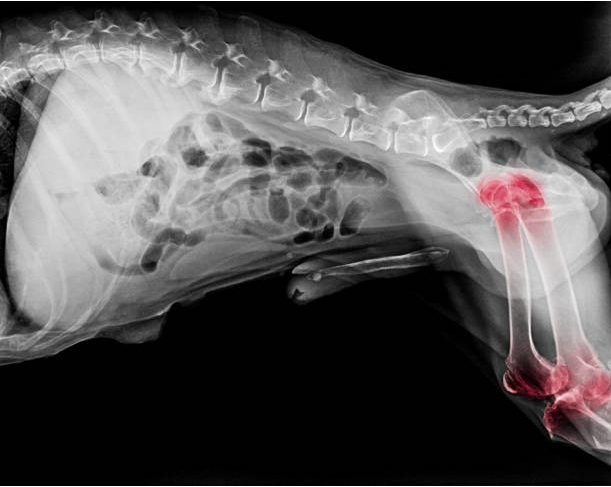

La displasia de cadera es una enfermedad ósea hereditaria que afecta a las articulaciones de la cadera de los perros. No es congénita, ya que las caderas son normales al nacer, sino que se desarrolla debido a un crecimiento desigual entre el sistema esquelético y los músculos.

Factores como el peso corporal, el tipo de ejercicio y las condiciones ambientales también pueden contribuir al desarrollo de la displasia de cadera. La frecuencia de displasia de cadera en el Pastor Blanco Suizo es del 19%. El diagnóstico de la displasia de cadera se basa en la información del propietario sobre el comportamiento del perro, así como en los signos clínicos y los datos radiográficos. Los síntomas clínicos pueden variar mucho de un individuo a otro e incluso pueden estar ausentes durante toda la vida del perro en muchos casos.

El diagnóstico radiográfico es especialmente valioso a partir de los 6 meses de edad. En cachorros de 3 a 4 meses, los síntomas pueden incluir dolor a la palpación de las caderas o al caminar. Si el dolor no es intenso, el cachorro puede mostrar sólo alteraciones de la marcha, debilidad en los cuartos traseros o tendencia a sentarse con frecuencia. El cachorro puede parecer torpe y tener músculos débiles en los cuartos traseros, con las patas traseras muy separadas y cruzadas. A medida que avanza la enfermedad, el cachorro puede experimentar dolor al caminar, lo que da lugar a una marcha característica de "conejito saltarín" y un movimiento excesivo de las caderas. En cachorros de 4 a 6 meses, el rápido crecimiento y el aumento de la actividad física pueden causar un dolor notable. El cachorro puede tumbarse y caer al suelo.

Radiográficamente, puede haber cambios en el borde acetabular y retraso en la conversión del fibrocartílago en cartílago hialino, junto con microfracturas y tensión en la cápsula articular y el ligamento redondo. En cachorros de 6 a 12 meses, la laxitud de la cápsula articular puede ser evidente tanto radiográficamente como mediante palpación. También puede haber dolor a la palpación y una marcha característica de "salto de conejo". En los perros adultos, la artrosis puede causar dolor tras el ejercicio prolongado o intenso, anomalías musculares durante el ejercicio, sinovitis, pasos cortos y disminución del movimiento de la cabeza femoral dentro del acetábulo. Estos perros pueden preferir sentarse a estar de pie y pueden presentar atrofia muscular en los muslos. La gravedad de la displasia de cadera puede clasificarse según la gradación de la FCI. El grado HDA indica que no hay signos de displasia, mientras que el grado HD E indica una displasia grave con anomalías y deformidades articulares marcadas. Existen tratamientos conservadores, terapéuticos y quirúrgicos para la displasia de cadera, pero ningún tratamiento puede restablecer totalmente la función normal de la articulación. El tratamiento conservador en perros jóvenes incluye limitar el ejercicio, controlar el aumento de peso y controlar el crecimiento rápido mediante el control de la dieta. Las opciones quirúrgicas incluyen la pectinectomía para aliviar el dolor y la triple osteotomía pélvica para corregir la inestabilidad articular. En conclusión, la displasia de cadera es una enfermedad ósea hereditaria que afecta a las articulaciones de la cadera de los perros. El diagnóstico se basa en los signos clínicos y los hallazgos radiográficos, y las opciones de tratamiento incluyen el tratamiento conservador y la cirugía. La gravedad de la displasia puede clasificarse según la gradación de la FCI.

La detección precoz y el tratamiento adecuado son cruciales para mejorar la calidad de vida de los perros con displasia de cadera.